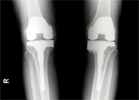

52 year old Malay male with chronic left knee pain due to unicompartmental arthritis

Pre

Op

Pre Operation Xrays

Post

Had unicompartmental knee replacement in view of relatively young age and monocompartmental arthritis